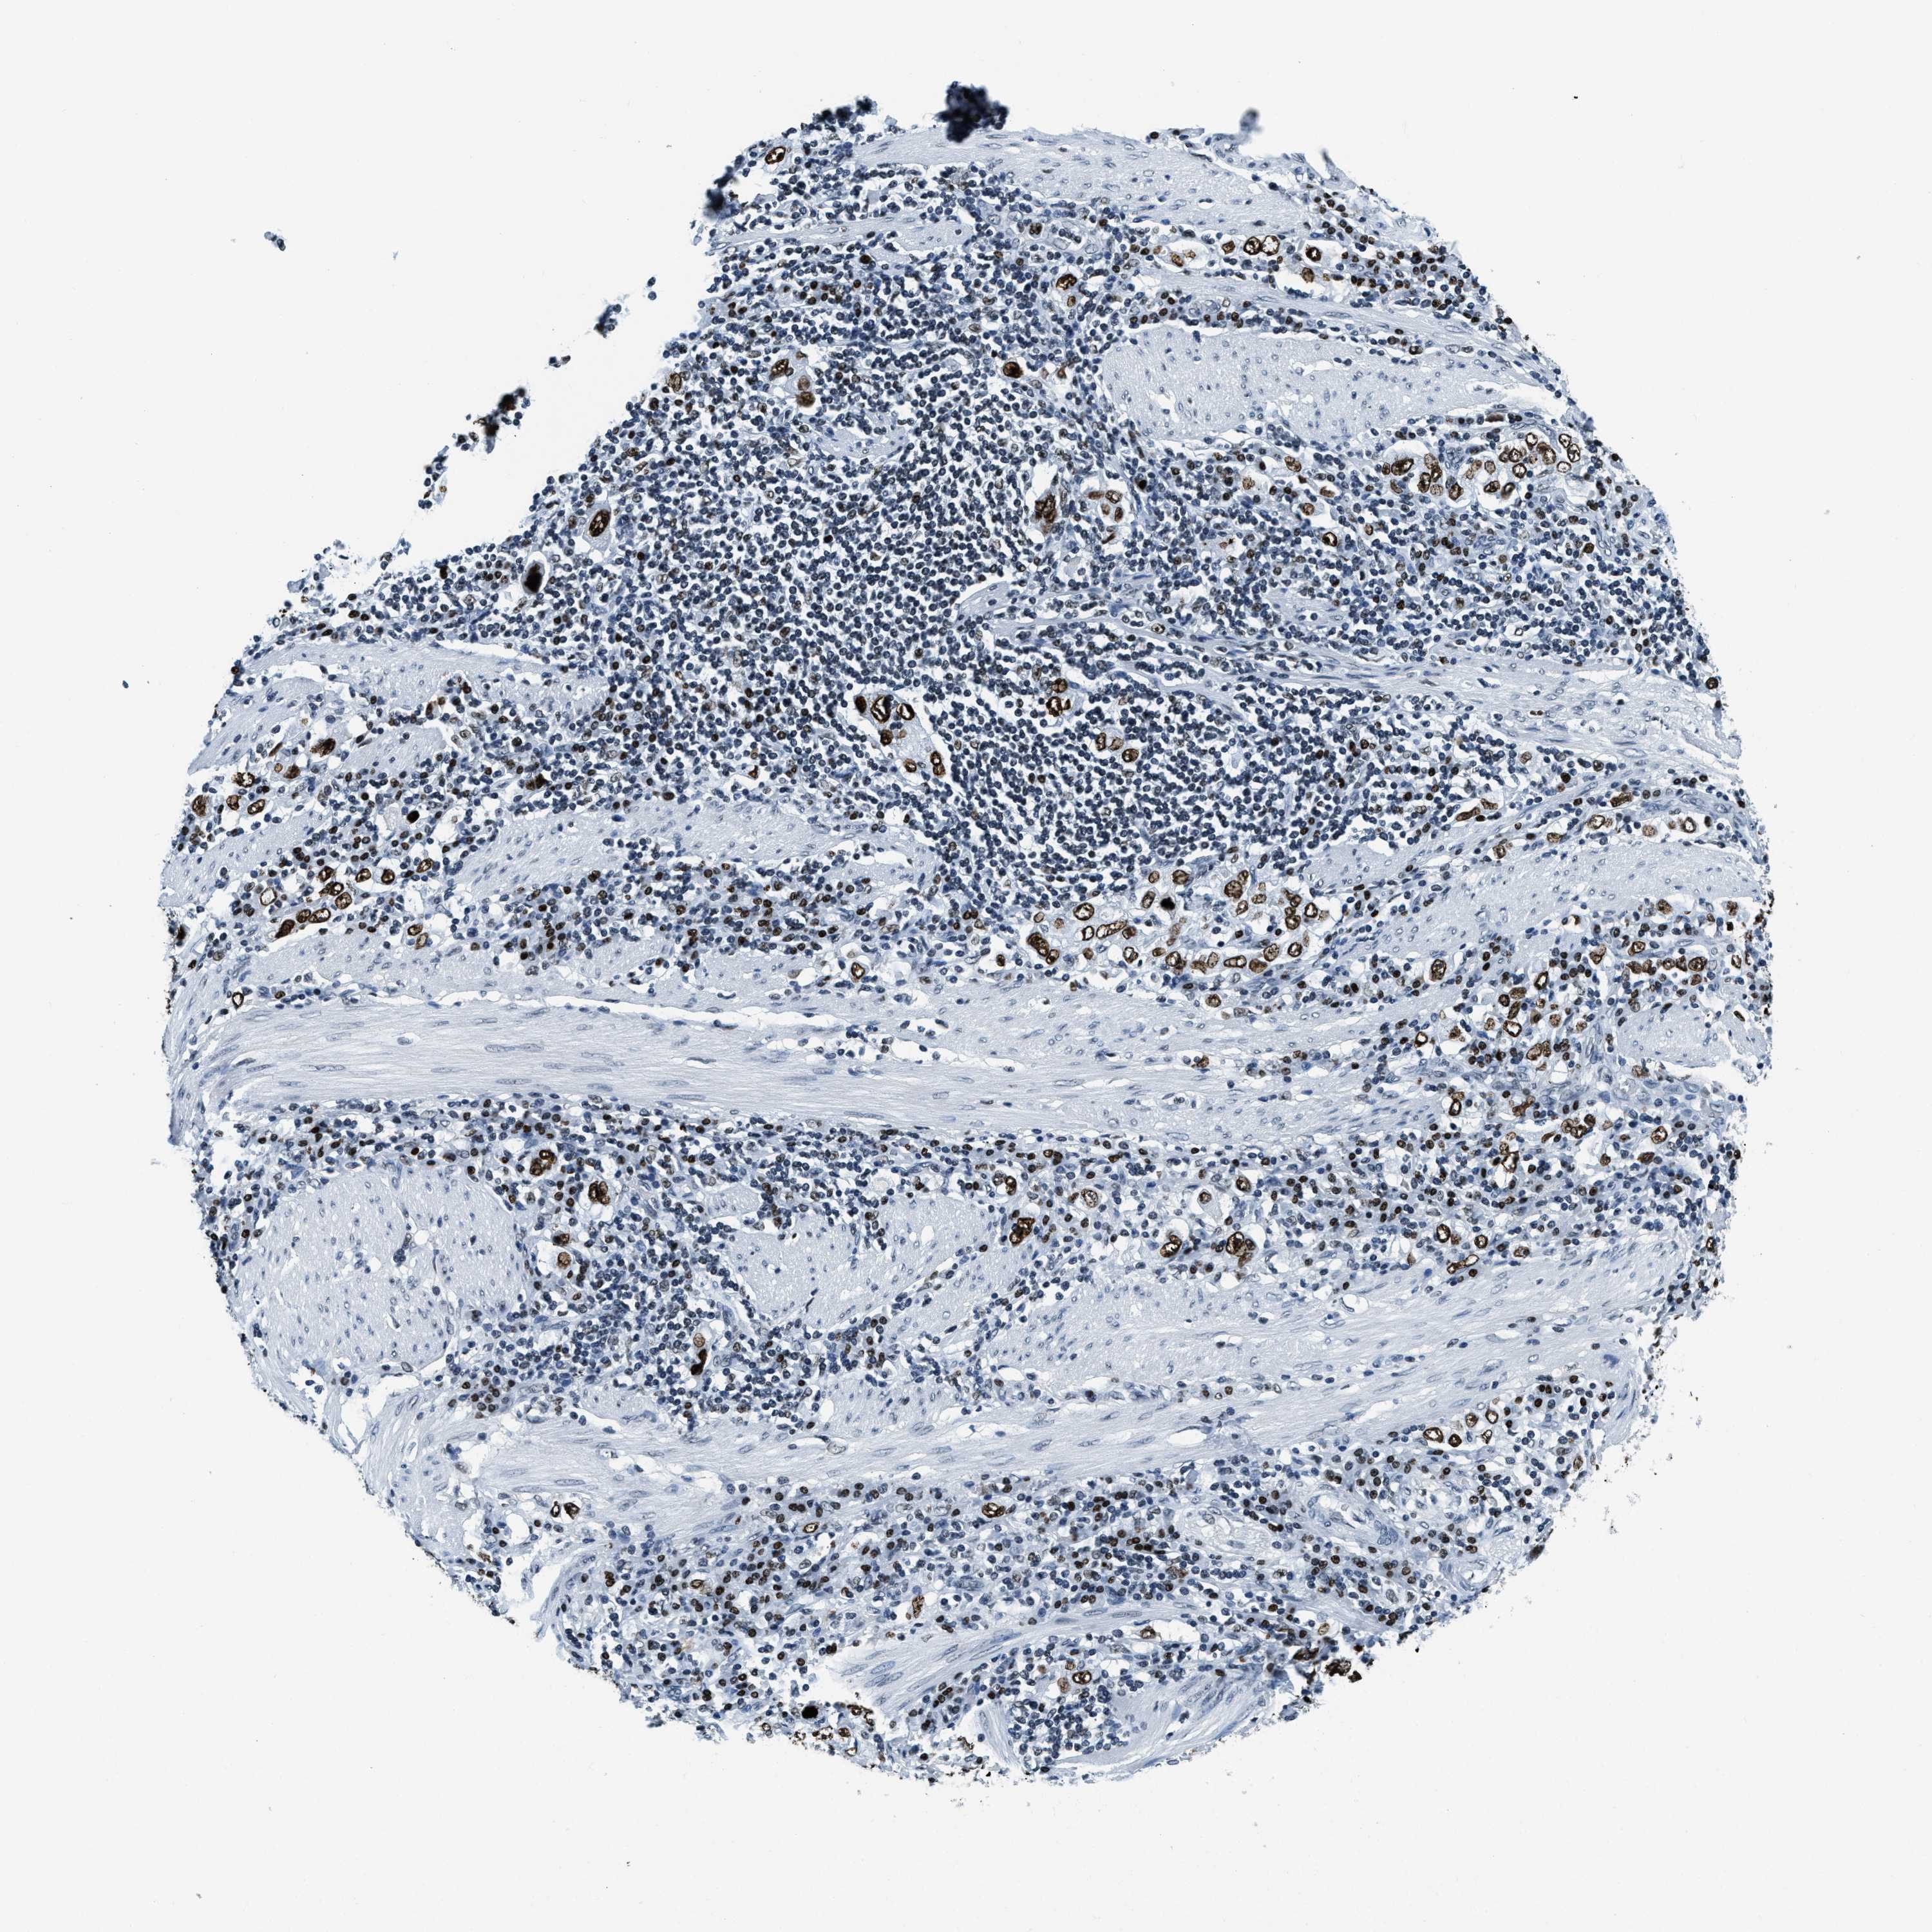

STOMACH CANCER - Protein expressioni

A mouse-over function shows sample information and annotation data. Click on an image to view it in a full screen mode. Samples can be filtered based on level of antibody staining by selecting one or several of the following categories: high, medium, low and not detected. The assay and annotation is described here.

Antibody stainingi

Antibody staining in the annotated cell types in the current human tissue is reported as not detected, low, medium, or high, based on conventional immunohistochemistry profiling in selected tissues. This score is based on the combination of the staining intensity and fraction of stained cells.

Each image is clickable and will lead to virtual microscopy that enables deeper exploration of all samples and also displays staining intensity scores, fraction scores and subcellular localization as well as patient and tissue information for each sample.

Antibody HPA019039

Antibody CAB009058

Staining

High

Medium

Low

Not detected

Intensity

Strong

Moderate

Weak

Negative

Quantity

>75%

75%-25%

<25%

None

Location

Nuclear

Cytoplasmic/membranous

Cytoplasmic/membranous,nuclear

Adenocarcinoma, NOS